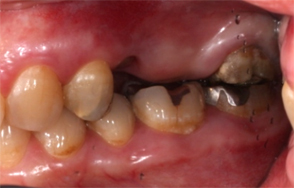

- インプラント治療前

- 主訴

- 左上ブリッジの支台であった左上5を歯根破折でばっしとなり左上56の欠損となった

- 治療内容

- 抜歯から3ヶ月の治癒期間を経てCT撮影を行った結果、通常であれば上顎洞挙上手術の対象となるケースが多いが、ショートインプラントを用いることで大規模な骨造成お回避できることがわかった。2本ショートインプラント埋入

- 治療費用

- 900,000円(税別)

- 治療期間

- 5ヶ月